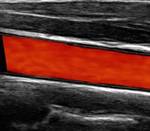

Gefäßplaque im Ultraschall

normales Gefäß